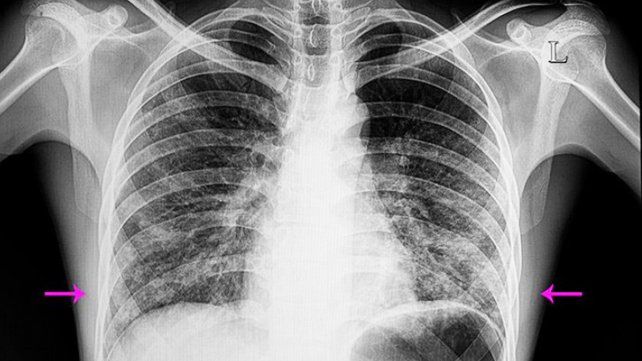

- El diagnóstico de la neumonía bilateral se hace a través de una radiografía del tórax. También es necesario realizar una exploración física y, una vez que se establece el diagnóstico, generalmente hacen falta otras pruebas para ver el tipo de gérmenes y el tipo de severidad.